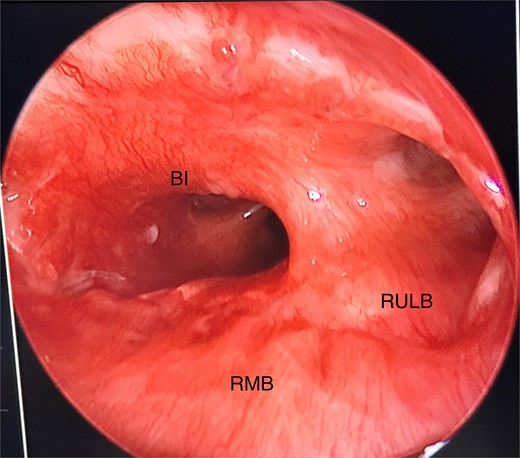

She initially underwent a rigid bronchoscopy, biopsy of the endobronchial tumour, cryoablation, and argon plasma for debulking. On direct visualization with the telescope the tumour was polypoid and was arising from the membranous portion of the right main bronchus (RMB) (Fig. 2).

Initial rigid bronchoscopy showing a polypoid mass originating from the membranous portion of the right main bronchus; BI, bronchus intermedius; RMB, right main bronchus.

Anomalous right bronchial anatomy was also noted (Fig. 3). The biopsy was sent for frozen section, which confirmed a carcinoid tumour.

Post disobliteration of the tumour through rigid bronchoscopy, also showing aberrant anatomy, where the apical segmental bronchus of the right upper lobe has a high take off at the distal trachea/carina; C, carina; RMB, right main bronchus; BI bronchus intermedius; RULB, right upper lobe bronchus; ASB, apical segmental bronchus.